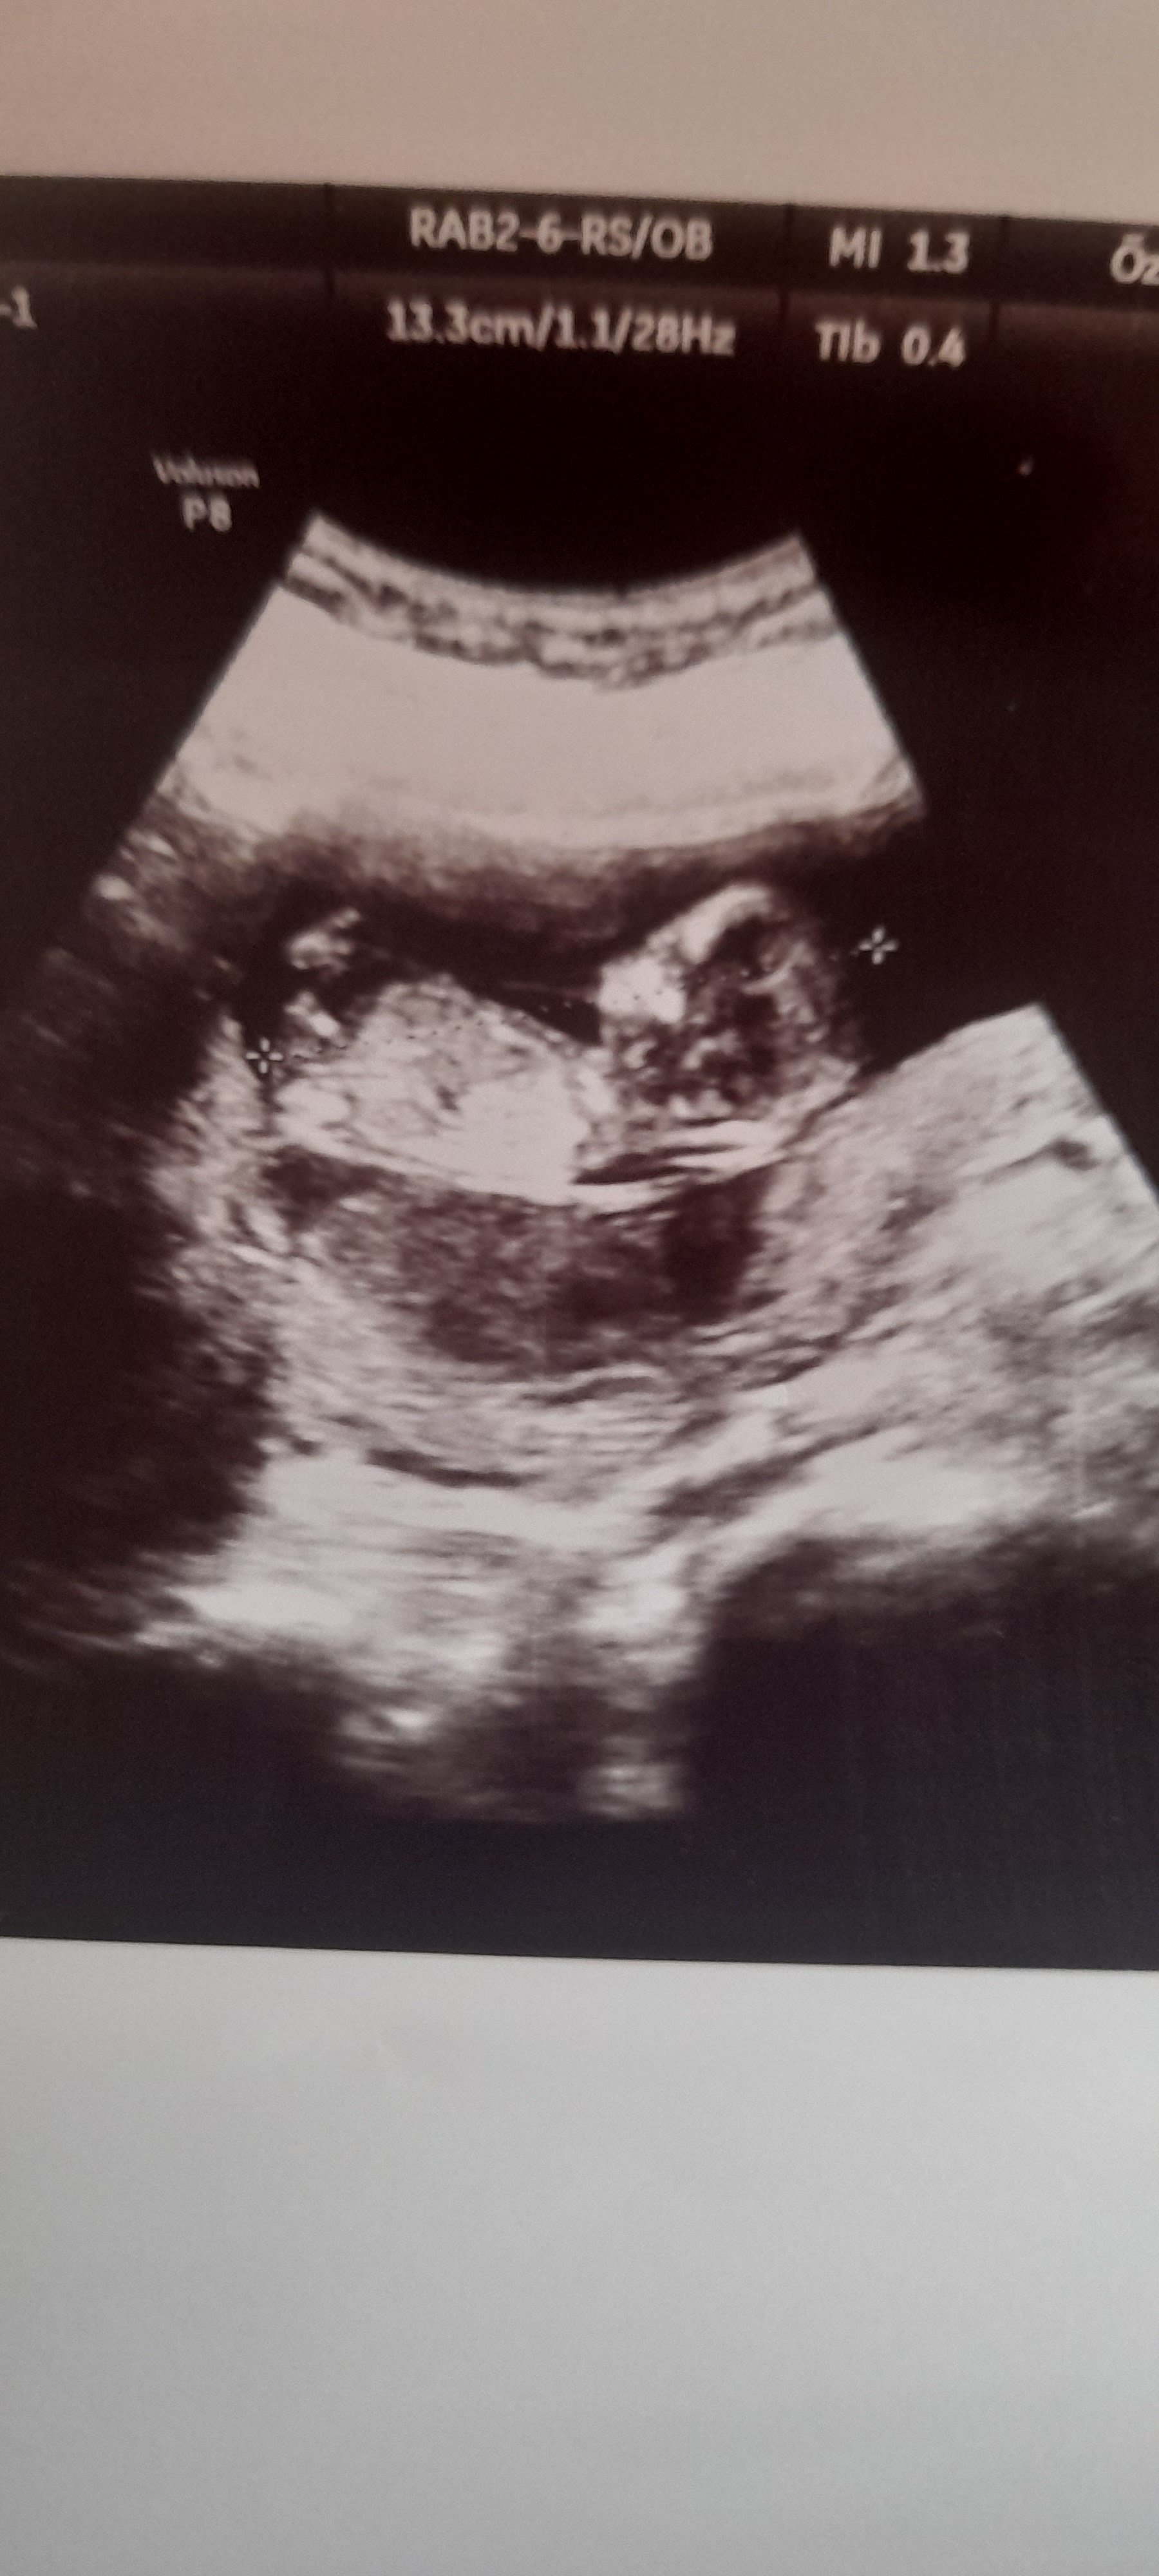

Kizlar doktor yine bilemedi cinsiyetini bi bakın fotoya

Ya tam bsy soyleyemedi bi çıkıntı gibi bsylerde görüyor ama kordonda olabilir diyor. Anlamadim gitti .d

Canısı o çıkıntı 16.haftaya kadar var tam net 20.haftada gelişimini tmamlıyo aslında😊